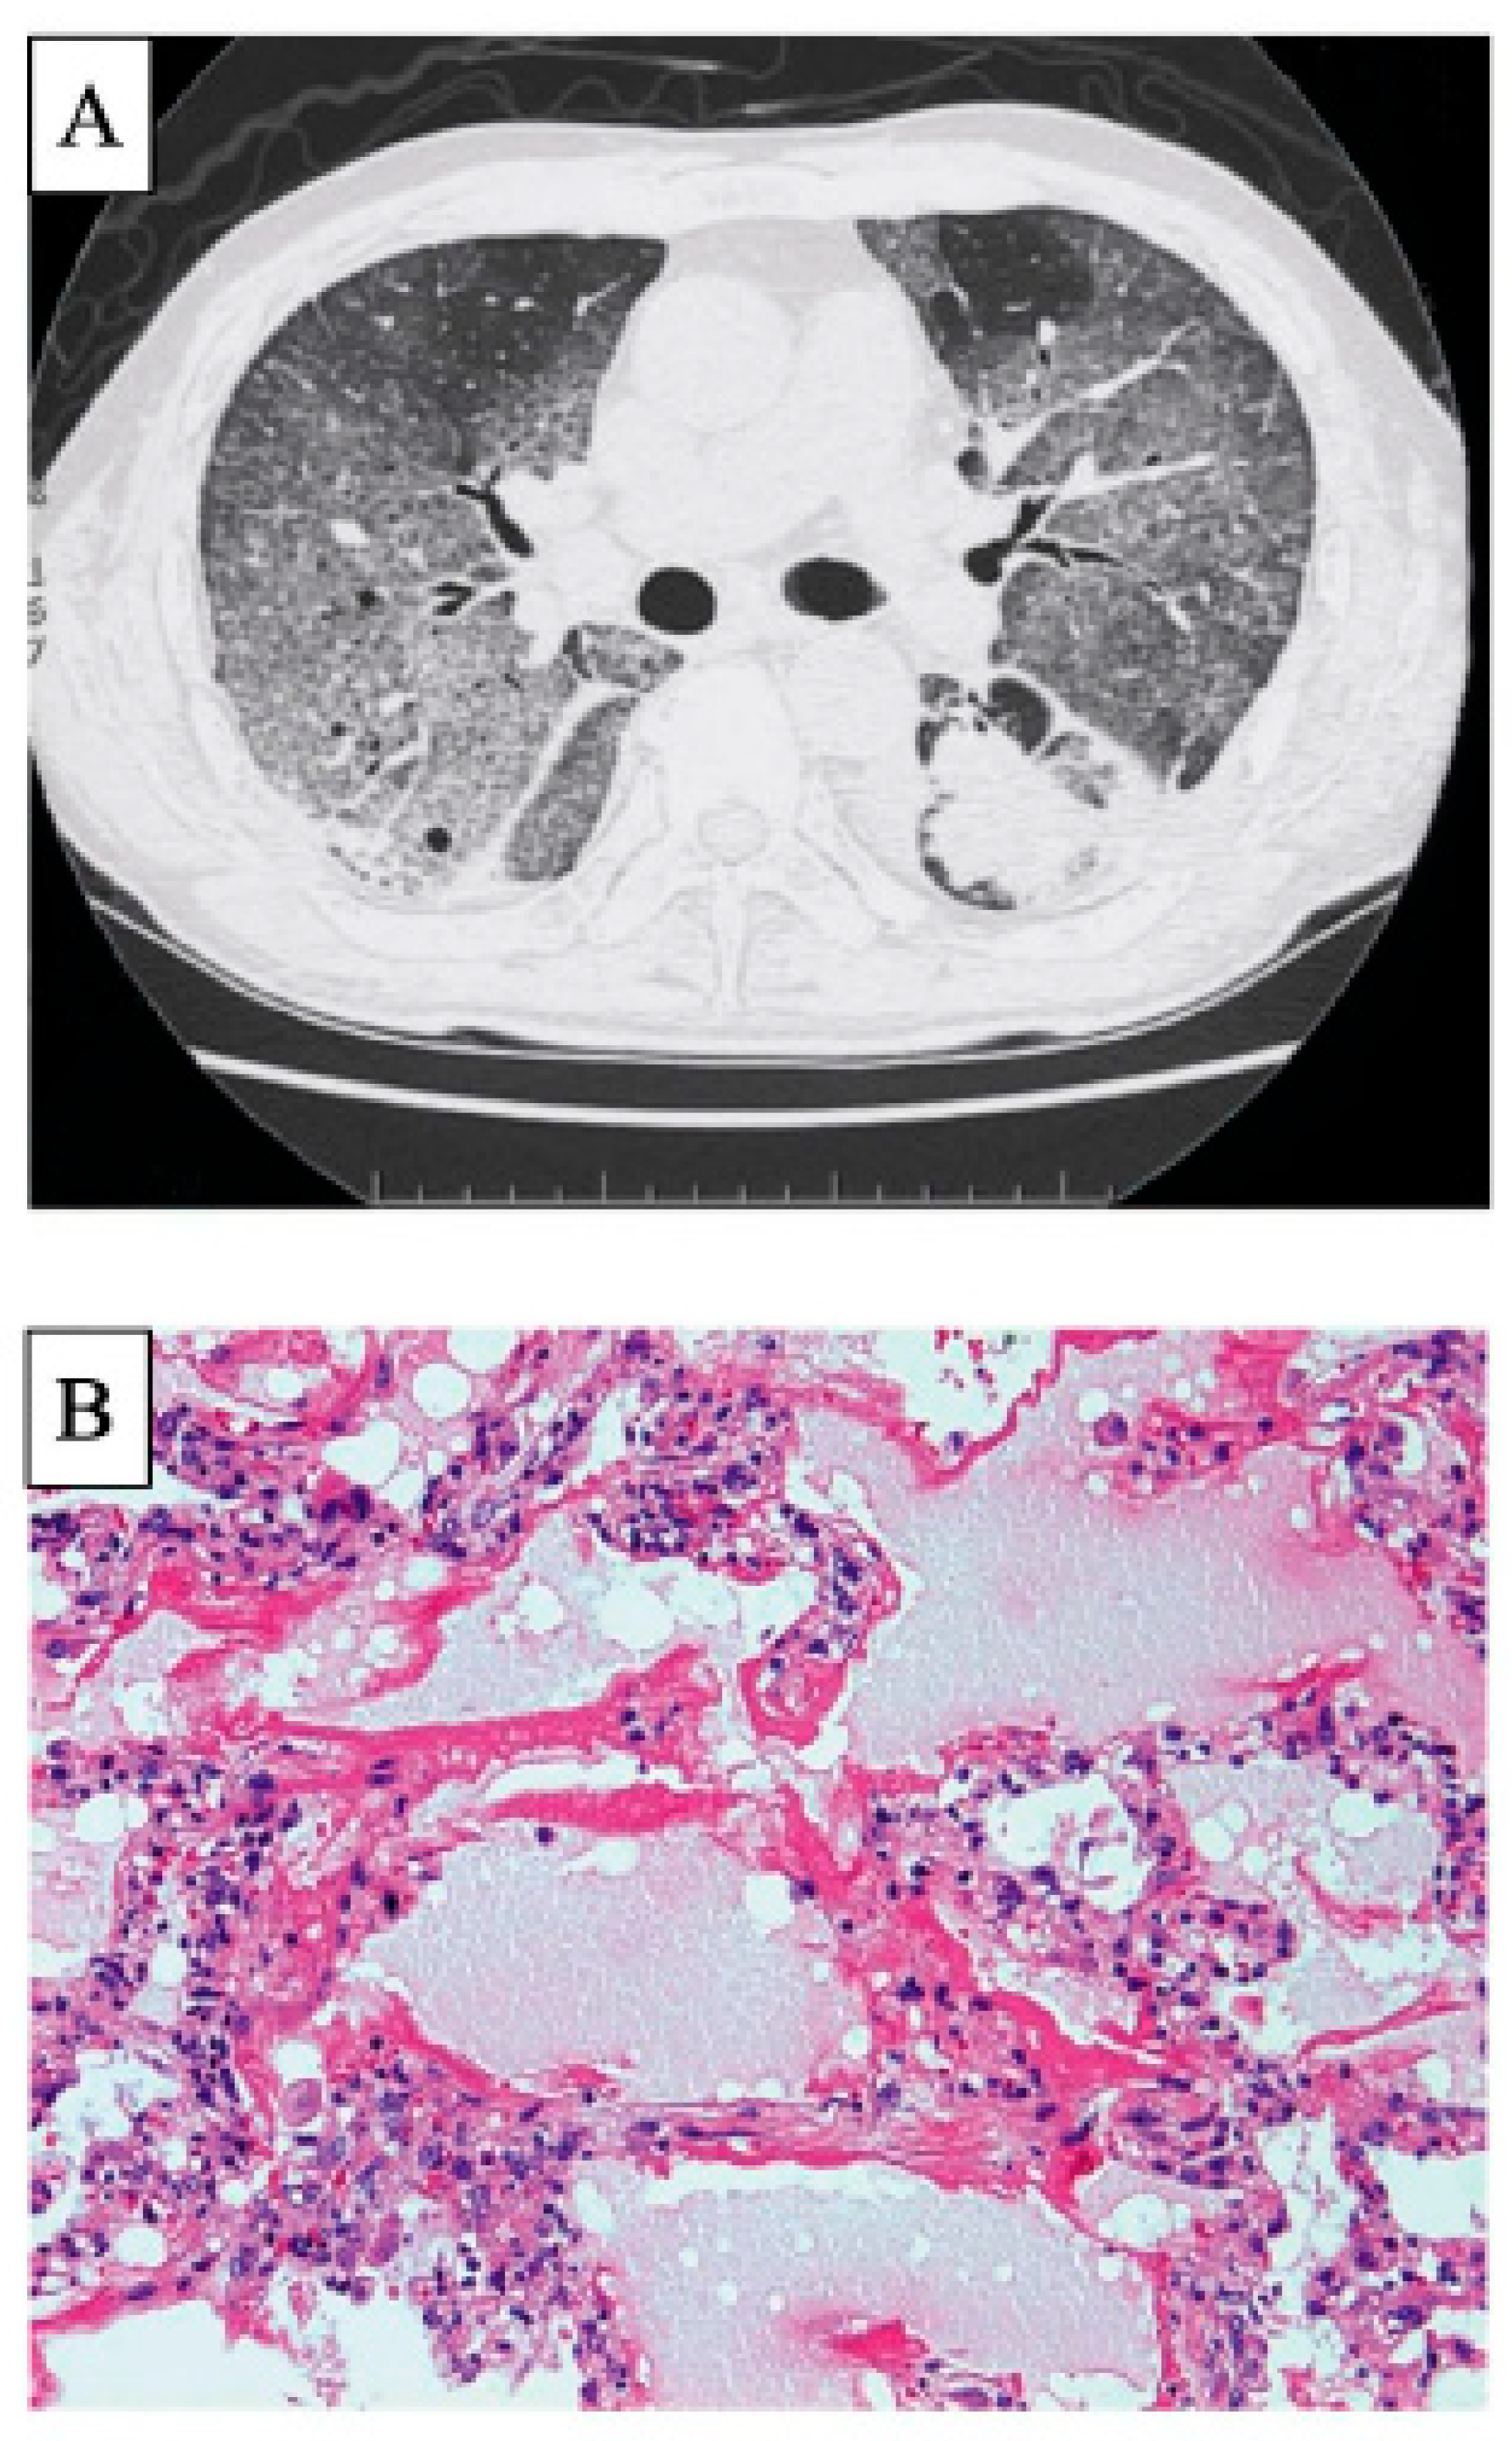

- Chino, H.; Sekine, A.; Baba, T.; Iwasawa, T.; Okudela, K.; Takemura, T.; Itoh, H.; Sato, S.; Suzuki, Y.; Ogura, T. Radiological and Pathological Correlation in Anti-MDA5 Antibody-positive Interstitial Lung Disease: Rapidly Progressive Perilobular Opacities and Diffuse Alveolar Damage. Intern. Med. 2016, 55, 2241–2246. [Google Scholar] [CrossRef] [PubMed]